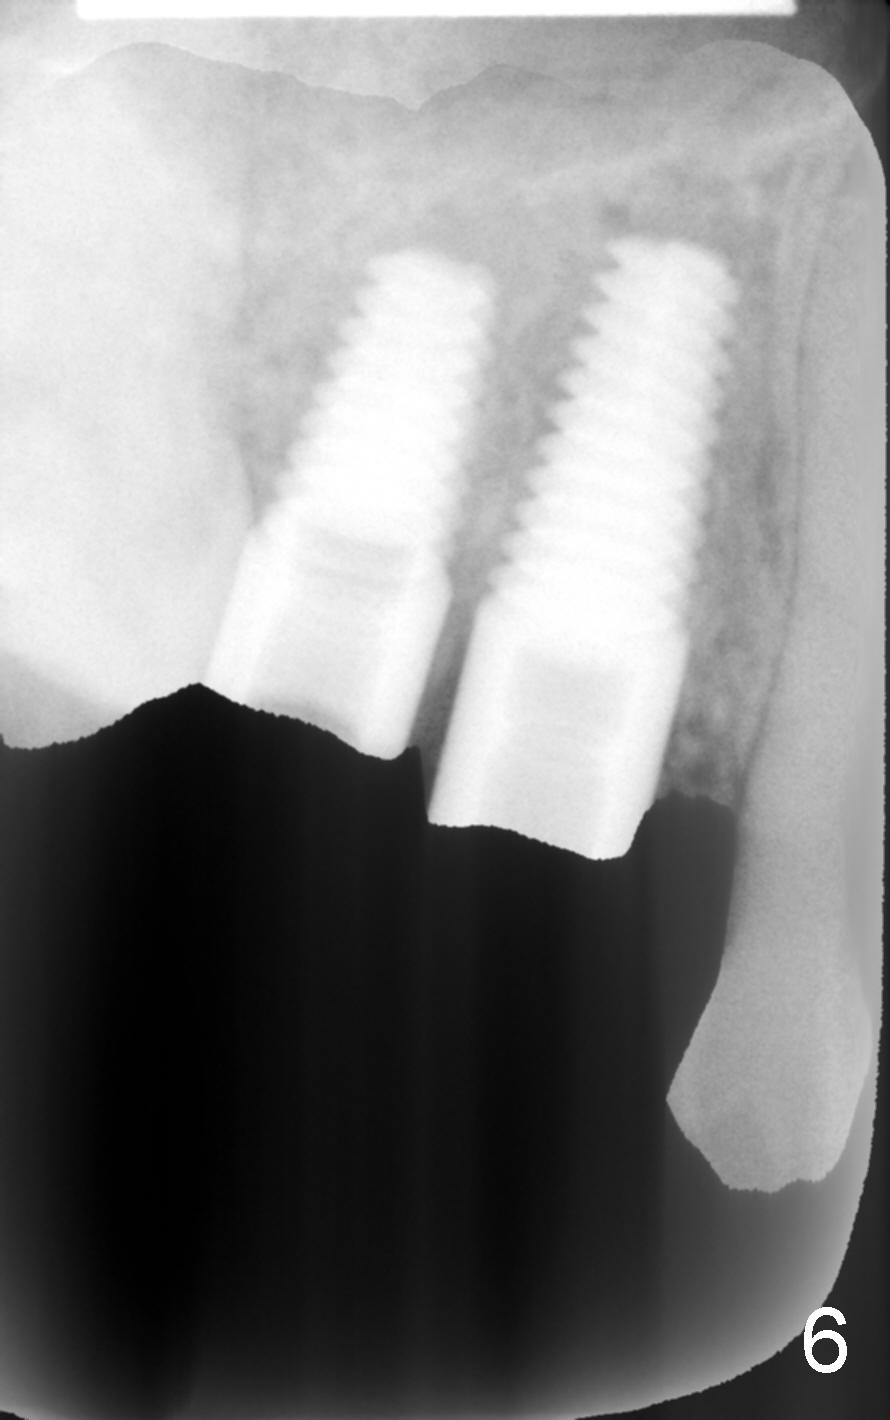

8. 4.5x17 tap, implants, torque wrench (4.5x11 and 4.5x14 mm tapered implants were placed at the sites of #4 and 5, respectively (Fig.6))

9. Fig.2,3 show pilot drill and guiding pin at the sites of #4 and 5, respectively.  Thanks to our joined effort, the axis of the implant at the site of #4 was corrected from Fig.4 to 6